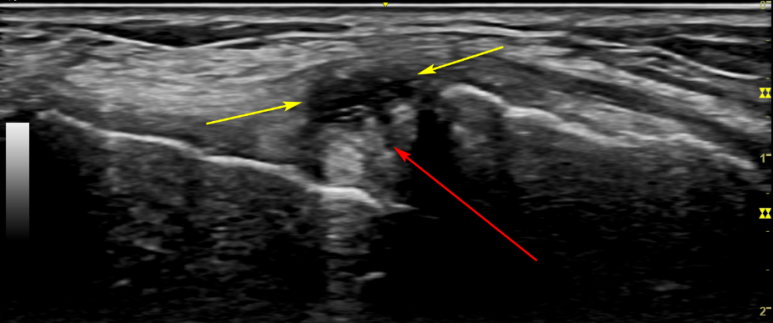

해당 환자분의 양구혈

그런데 이 환자분은 정상 초음파와 다른 모습이죠?

빨간 화살표 부분이 까맣게 물이 찬 것이 보입니다.

가져오신 MRI 영상의 내측 반월상 연골 파열

가져오신 MRI 영상과

음곡혈 초음파를 비교해보니

내측 반월상 연골 파열(빨간 화살표)과

파열 부위와 연결된 반월판 낭종(노란 화살표)이

보입니다.

특히 저 물혹을 눌러보면 아주 심한 통증이 나타났는데, 뽑아보니 아주 끈끈한 젤라틱 점액이 꽉 차있었습니다.

최근 들어 악화된 통증은 반월판 낭종이 주변 조직을 압박하면서 생겼을 가능성이 있었습니다.